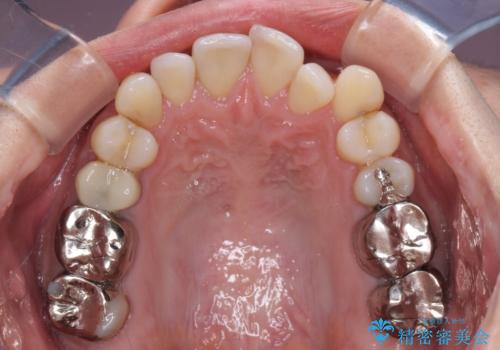

受け口傾向の咬み合わせ 前歯のデコボコをワイヤー矯正で素早く改善

- 前歯の見た目を気にして来院された患者様です。

前歯のクロスバイトは、改善の途中で歯髄壊死を起こすリスクが高くなるため、マウスピース矯正よりもワイヤー矯正をお勧めしております。

この患者様もクロスバイトはあっという間に改善され、1年強で速やかに治療を終えることができました。